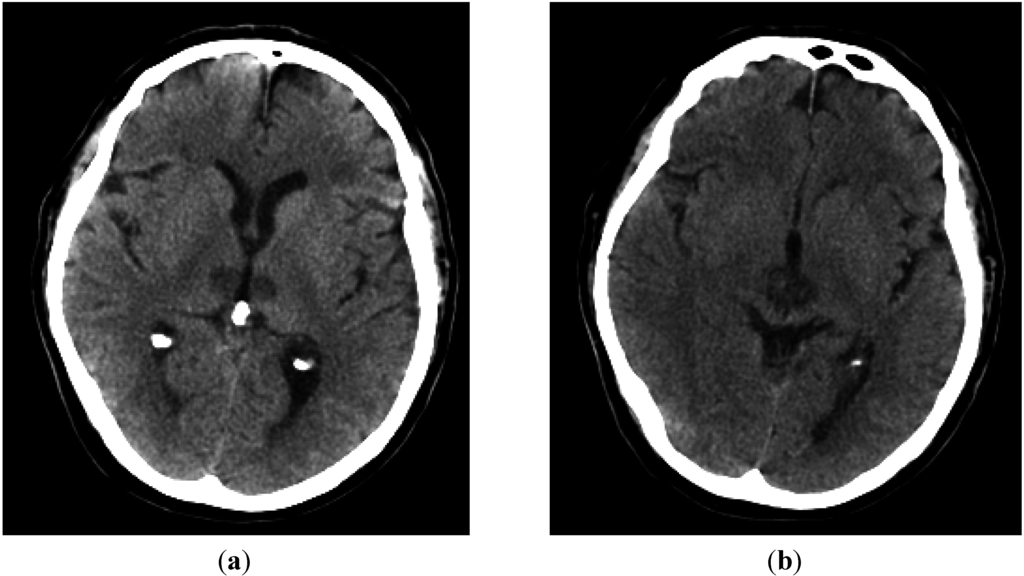

A Case of Midbrain and Thalamic Infarction Involving Artery of Percheron

2. Case Report